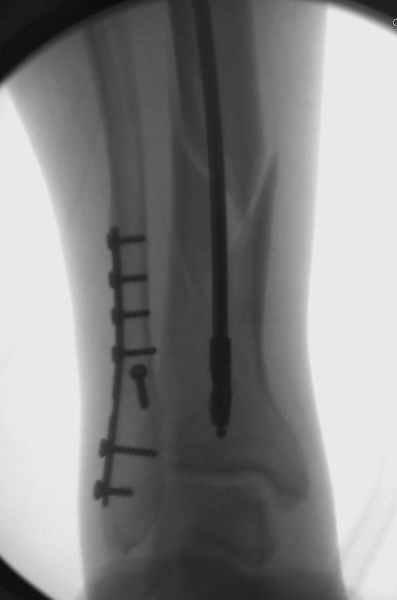

Здесь мы использовали новый Synthes Nail с дополнительными дырками, в проксимальной части 4: по две косых и поперечные (один стандартный а другой динамический), в дистальной части две поперечные, прямая и косая. Вес больного более 120 кг, нагрузку начнем через месяц.

Получилось красиво, поздравляю. Вверху можно было ограничиться одним винтом во фронтальное статическое отверстие, зачем два 45-градусных?

При такий спирали задний край tibia может быть сломан - нет ли этого в данном случае? На всякий случай можно было ввести 1-2 винта 4,5 мм спереди назад мимо гвоздя. Хотя самый дистальный блокирующий винт, возможно, зацепил этот отломок. А какой тут диаметр гвоздя и locking винтов?